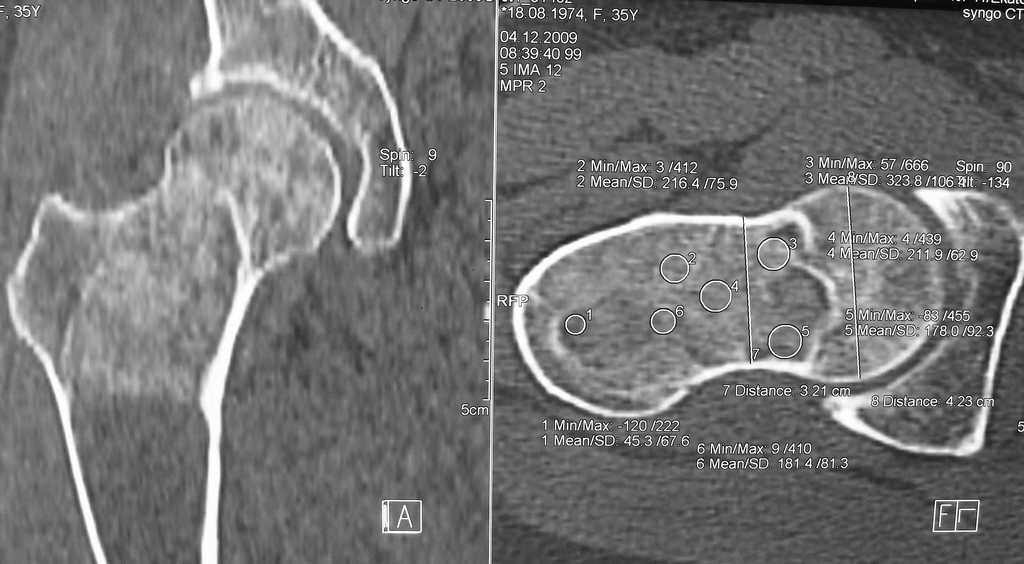

Уважаемые коллеги, доброго времени суток!

Большое спасибо всем, откликнувшимся на сообщение от 17 ноября

"Фиброзная дисплазия". В настоящее время пациентке выполнена

компьютерная томография и открытая биопсия правой бедренной кости с

последующим иммуно-гистохимическим исследованием.

Подтверждается диагноз фиброзной дисплазии без малигнизации.

Хотелось бы услышать мнение коллег относительно тактики дальнейшего

лечения пациентки, в первую очередь, варианты замещения дефекта в

случае резекции патологического очага с учётом обширности поражения.